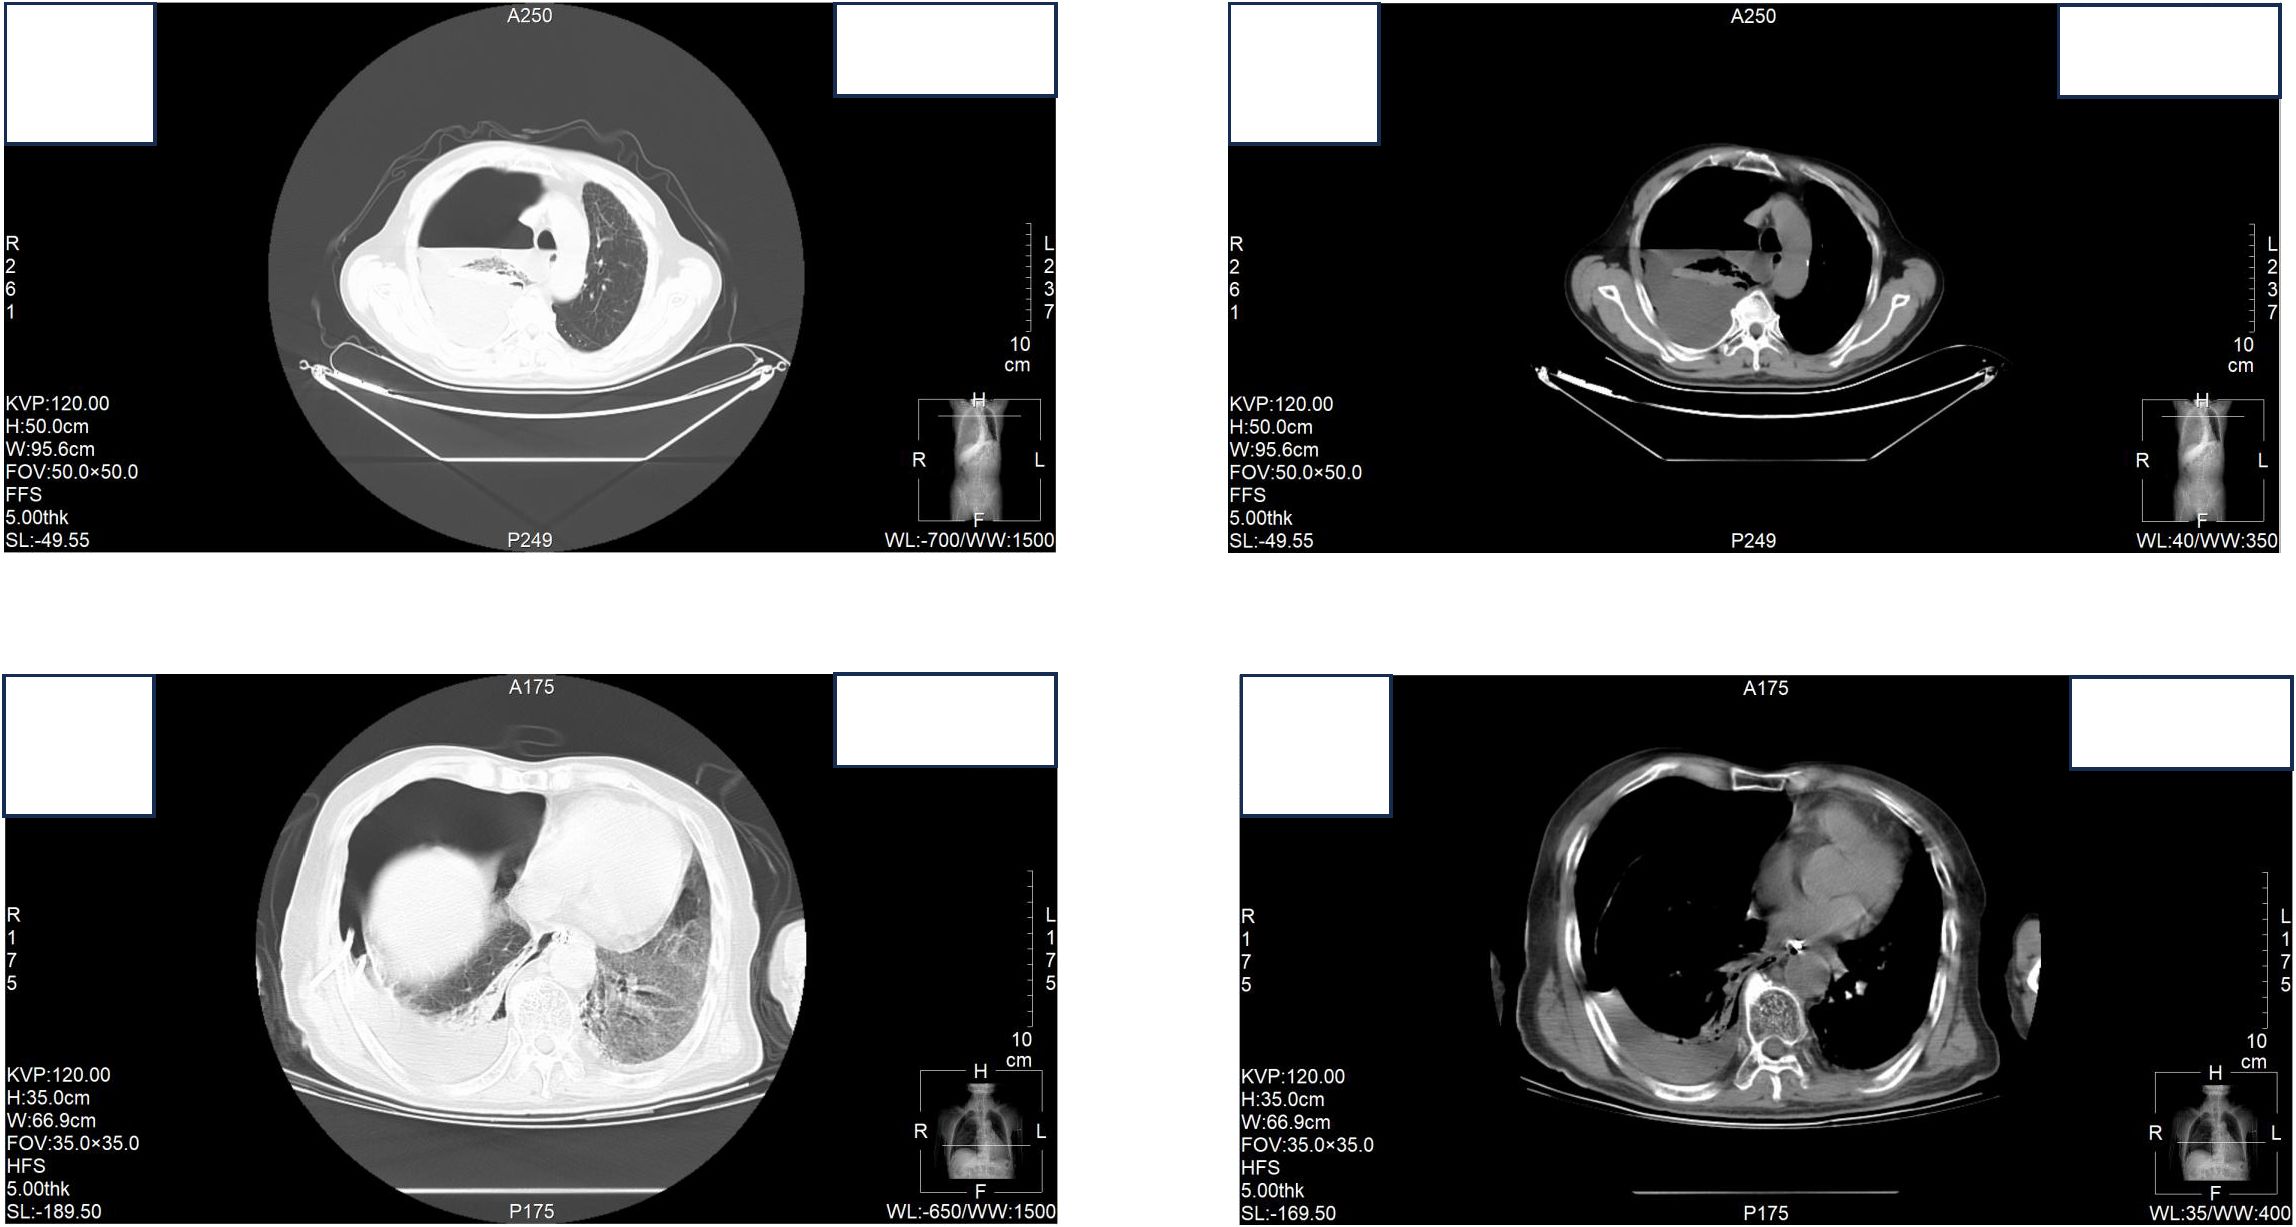

At the time of hospitalization, her vital signs were stable (temperature 36.5 °C, pulse rate 67 bpm, blood pressure 133/68 mm Hg, respiratory rate 18 breaths/min). The physical examination of the respiratory system revealed that breath sounds in the right lung were slightly diminished. No other positive clinical signs were noted. A contrast-enhanced CT scan of the chest demonstrated pleural effusion and hydropneumothorax in the right thoracic cavity (Figure 1). There was no evidence of metastatic lesions, lung parenchymal lesions or regional adenopathy on the CT scan. Therefore, it is possible that EPF may be obscured. Consequently, thoracic drainage was performed to collect hydrothorax for laboratory and pathologic inspection. The laboratory physician identified normal squamous cells within the hydrothorax and communicated these findings to the clinical team. The indictors of Interleukin-6, tumor markers, routine and biochemical test of pleural effusion indicted the inflammation (Table 1). The leukocyte count was recorded at 14.26*10^9/L with neutrophils constituting approximately 90.80% of total white blood cells. The Rivalta test for the pleural effusion yield a positive result. The nucleated cell count number was at 17343*10^6/L. The chlorine level was recorded at 105.1 mmol/L, while the glucose level was found to be 3.45 mmol/L. The total protein concentration was less than 20.00 g/L (Table 1). Simultaneously, acid-fast staining and microbial mass spectrometry analysis were conducted by the laboratory personnel (Figure 2). The appearance of fluid was yellow and turbid; typically, it is faint yellow and transparent (Figure 3A). Negative results from acid-fast staining effectively ruled out Mycobacterium tuberculosis infection while microbial mass spectrometry confirmed an infection with Staphylococcus epidermidis. Pathological exfoliated cytology did not reveal any tumor cells nor evidence of cancer recurrence.

Figure 1. Contrast-enhanced CT scan of the chest demonstrated pleural effusion and hydropneumothorax in the right thoracic cavity.